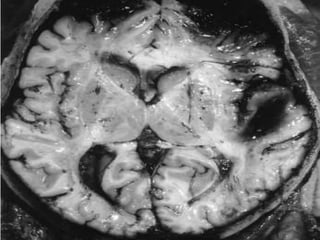

mli1. Evidence of application of blunt force. Accidental Homicidal Suicidal – Unusual ARTIFICIAL BRUISES 2. Though in itself a trivial injury, Lies in the site & the organs involved. Contusion of vital organs heart and brain.Caused marked derangement of functions & even death

3. Volume of blood- Circulating Diminished – Due to Extravasation4. Patterned Bruising Nature of agent used.5. Healing – Determination of age.6. Bruising- Scalp- It is better. 7. Bruising over the particular part of the body-Indicate some peculiar offence Ex : On the Neck Inner Side of Thigh – FemalesIndicate Sexual Assault    small bruises The so called “six Penny Bruises”8.Character & manner of injury may be known from its distribution.

complications1. Contusion contain 20- 30 ml of blood or even more. Multiple contusion can cause death from shock & internal haemorrhages.2. Gangrene & death of tissue.3.Good site for Bacterial growth.

Internal bleeding due to ruptures of vessels and bleeding into body cavities – like pericardium, peritoneum, pleura and cranium.  Causes of death due to injury:

Late causes: Disseminated Intravascular Coagulation:Follows whole range of traumatic, infective and other acute events. Abnormal activation of coagulation process.Brain and placenta are particularly potent. Causes of death due to injury:

mli1. Evidence ofapplication of blunt force. Accidental Homicidal Suicidal – Unusual ARTIFICIAL BRUISES 2. Though in itself a trivial injury, Lies in the site & the organs involved. Contusion of vital organs heart and brain.Caused marked derangement of functions & even death

3. Volume ofblood- Circulating Diminished – Due to Extravasation4. Patterned Bruising Nature of agent used.5. Healing – Determination of age.6. Bruising- Scalp- It is better. 7. Bruising over the particular part of the body-Indicate some peculiar offence Ex : On the Neck Inner Side of Thigh – FemalesIndicate Sexual Assault small bruises The so called “six Penny Bruises”8.Character & manner of injury may be known from its distribution.

complications1. Contusion contain20- 30 ml of blood or even more. Multiple contusion can cause death from shock & internal haemorrhages.2. Gangrene & death of tissue.3.Good site for Bacterial growth.

Internal bleeding dueto ruptures of vessels and bleeding into body cavities – like pericardium, peritoneum, pleura and cranium. Causes of death due to injury:

Late causes: DisseminatedIntravascular Coagulation:Follows whole range of traumatic, infective and other acute events. Abnormal activation of coagulation process.Brain and placenta are particularly potent. Causes of death due to injury: